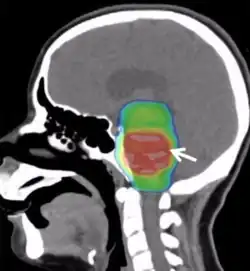

Radiotherapy for a young adult patient with a diffuse intrinsic pontine glioma. Color indicates radiation dose.

Conventional radiotherapy, limited to the involved area of tumour, is the mainstay of treatment for DIPG. A total radiation dosage ranging from 5400 to 6000 cGy, administered in daily fractions of 150 to 200 cGy over 6 weeks, is standard. Hyperfractionated (twice-daily) radiotherapy was used previously to deliver higher radiation dosages, but did not lead to improved survival. Radiosurgery (e.g., gamma knife or cyberknife) has a role in the treatment of DIPG and may be considered in selected cases.